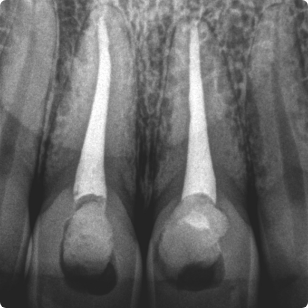

RTG punktowe zęba to zdjęcie tworzone przy wykorzystaniu promieni rentgenowskich, służące do oceny stanu konkretnego, pojedynczego zęba. To najczęściej wykonywana procedura radiologii stomatologicznej. Czy RTG jest niebezpieczne dla zdrowia? Nie. Dawka promieniowania przy takim badaniu wynosi zaledwie do 5 µSv (dla porównania dawka promieniowana przyjmowana codziennie przez mieszkańca Polski pochodząca ze źródeł naturalnych to 6,8 µSv), co czyni badanie obojętnym dla zdrowia pacjenta.